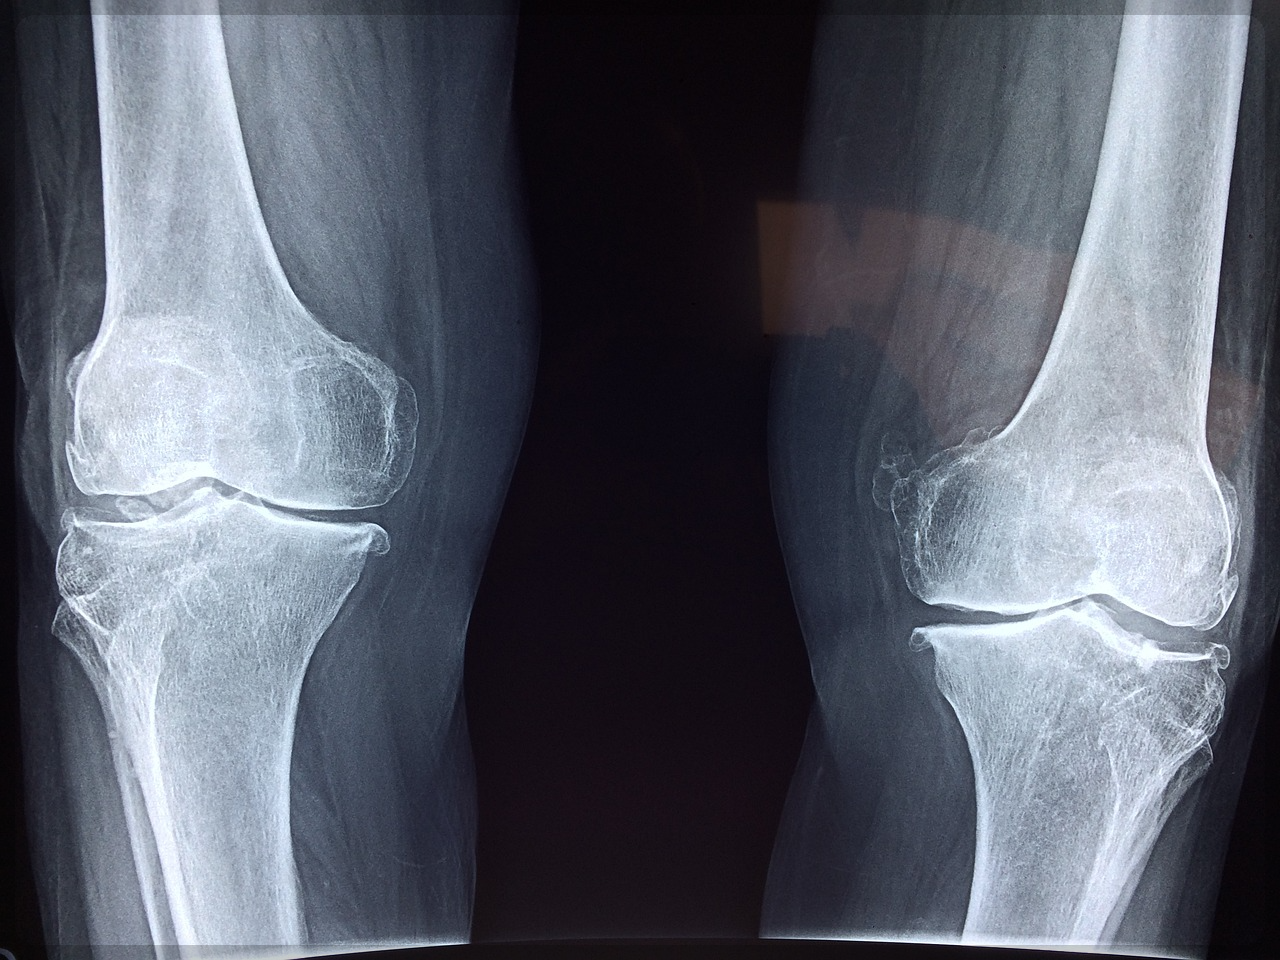

관절염은 나이가 들면 누구나 겪는 질환으로, 무릎, 손, 발, 허리 등 관절이 있는 부위에 통증, 붓기, 뻣뻣함 등의

증상이 나타납니다.

관절염은 크게 퇴행성 관절염과 염증성 관절염으로 나눌 수 있는데요

퇴행성 관절염은 노화로 인해 연골이 자연스럽게 손상되어 발생하는 질환으로, 여성에게서 더 많이 나타납니다.

1. 관절염, 왜 위험할까요?

관절염은 단순히 통증을 유발하는 것만이 아니라, 삶의 질을 크게 떨어뜨릴 수 있는 질환입니다.